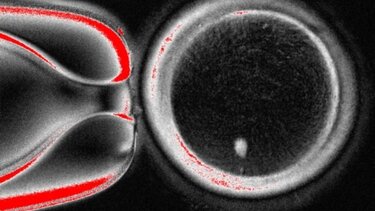

Στην κεντρική φωτο:

Ανθρώπινο ωάριο που δημιουργήθηκε μέσω μεταφοράς πυρήνα σωματικού κυττάρου

Η ομάδα του Όρεγκον ακολούθησε παρόμοια προσέγγιση, συλλέγοντας δερματικά κύτταρα από γυναίκες και αφαιρώντας τον πυρήνα από κάθε κύτταρο. Ο πυρήνας περιέχει τα 46 χρωμοσώματα που φέρουν περίπου 20.000 γονίδια που αποτελούν τον ανθρώπινο γενετικό κώδικα. Κάθε πυρήνας δερματικού κυττάρου τοποθετήθηκε σε ένα υγιές ωάριο δότη, του οποίου ο δικός του πυρήνας είχε αφαιρεθεί.

Σε άρθρο της που δημοσιεύθηκε στο επιστημονικό περιοδικό Nature Communications, η ερευνητική ομάδα περιγράφει πώς ξεπέρασε το πρόβλημα των χρωμοσωμάτων. Μετά τη γονιμοποίηση των ωαρίων με σπέρμα, τα ενεργοποίησαν χρησιμοποιώντας μια ένωση που ονομάζεται ροσκοβιτίνη. Αυτό είχε ως αποτέλεσμα τα ωάρια να μεταφέρουν περίπου τα μισά από τα χρωμοσώματά τους σε μια δομή που ονομάζεται πολικό σωμάτιο, αφήνοντας τα υπόλοιπα χρωμοσώματα να ζευγαρώσουν με αυτά του σπέρματος.